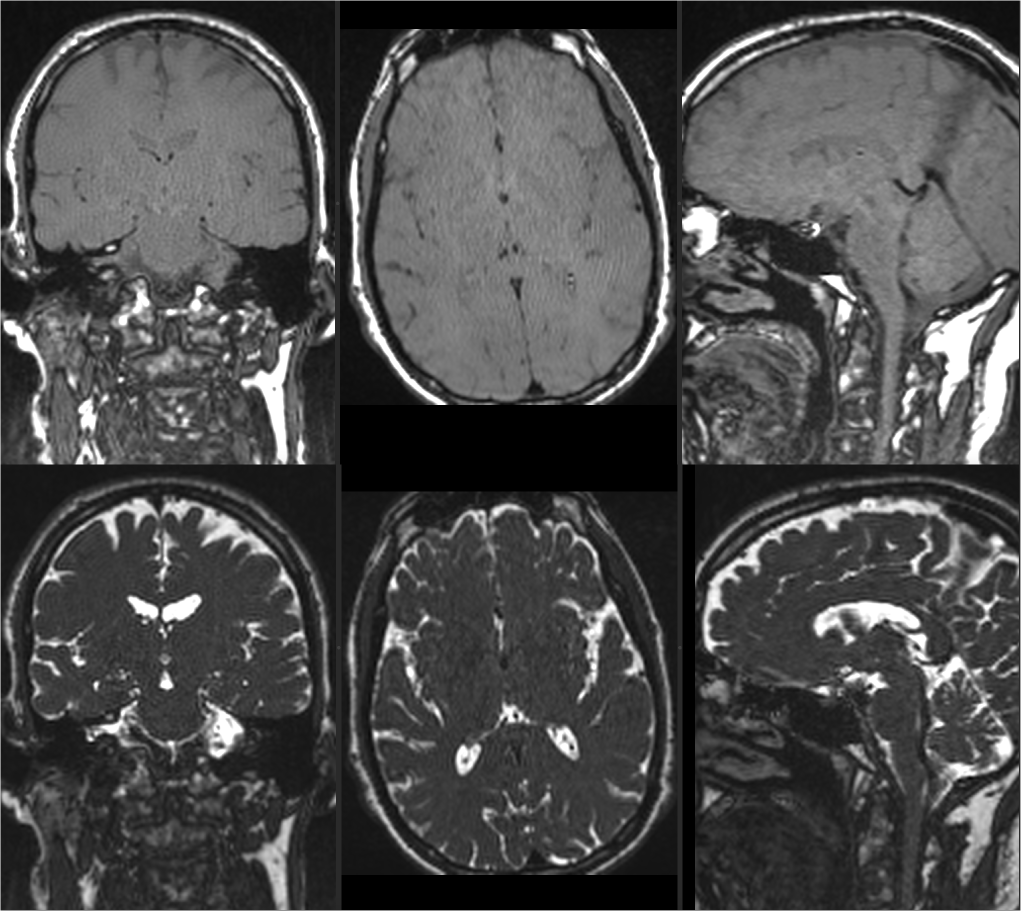

Results

Figure 2 and 3 compare images acquired with bSSFP and bT1RESS at 3T and 0.55T. The signal intensity of the CSF is suppressed using bT1RESS through periodic application of CM pulses. Banding artifacts appear at 3T near air-tissue boundaries and are absent at 0.55T. Figure 4 shows uT1RESS images acquired at 3T for CM flip angles of 0° and 90°. As in bT1RESS, the CM pulses generate T1 weighting and suppress CSF. The weak spoilers render the blood vessels dark, which appear bright in the spoiled 3D GRE images and may impact lesion visibility. Banding artifacts are absent with uT1RESS compared to bT1RESS at the same field strength. Figure 5 shows the corresponding isotropic uT1RESS scans in coronal orientation.

Fig 5: Isotropic images acquired at 3T with the uT1RESS sequence in coronal orientation using a CM flip angle of (top) 90°, which creates T1 weighting of the image contrast, and (bottom) 0° for reference.